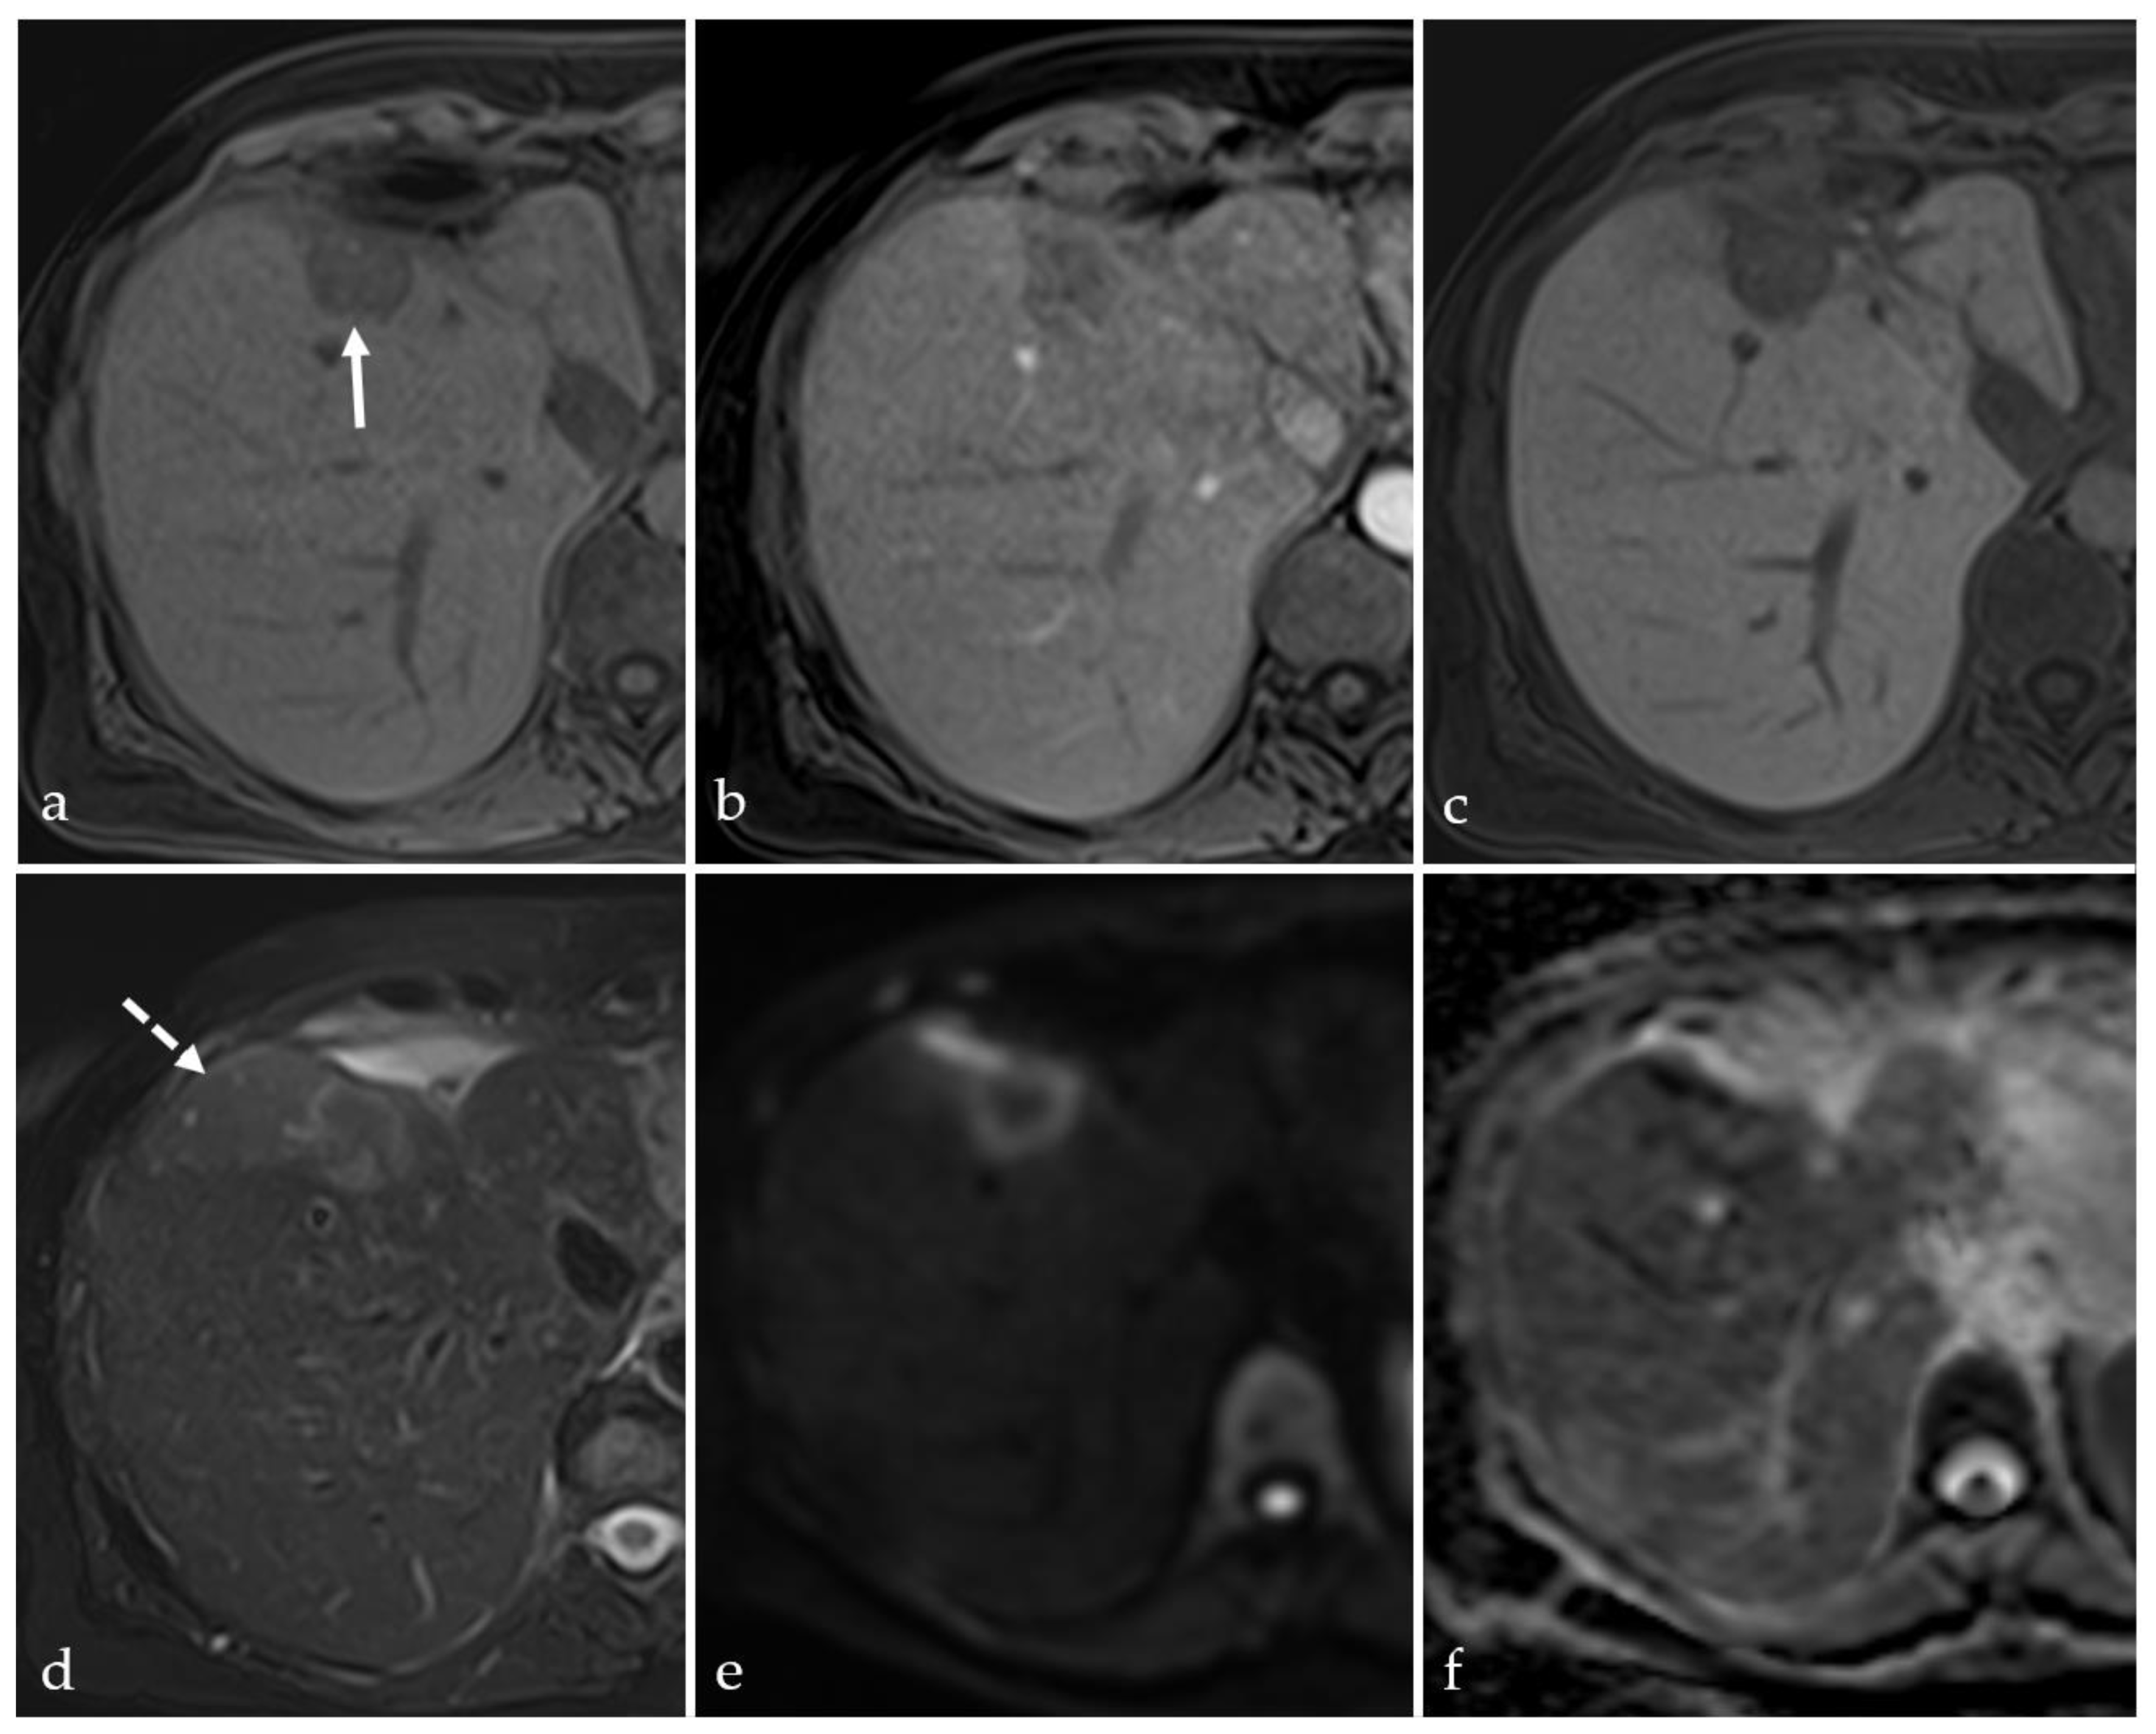

3.2. Expected Post-Treatment Imaging Features in the Absence of Viable Tumor Tissue

3.3. Transient Hyperemia

3.5. Post-Treatment Imaging Features of Tumor Viability